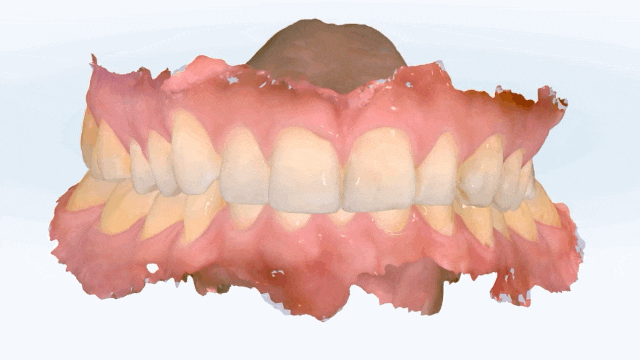

iTero 구강스캔

이러한 부분들을 모두 개선하기 위해서는 전체 재교정이 필요한 상태였습니다. 그러나 환자분께서 직업 특성상 빠른 시간 안에 최소한으로 치료를 원하셨기 때문에 환자분께서 가장 고치고 싶어하는 부위인 위 앞니 치열만을 개선하기 위해 라미네이트 치료를 하는 방법과 인비절라인으로 치료하는 방법의 두 가지를 설명드렸습니다.

치아 사이즈 및 형태를 개선시키기 위하여 최소삭제(무삭제) 라미네이트와 2~3개월 안에 마무리 가능한 인비절라인 익스프레스 장치를 추천드렸습니다. 환자분께서는 짧은 기간 안에 본인의 치아에 크게 손을 대지 않고 치료가 가능한 인비절라인 익스프레스 장치를 선택하셨습니다.